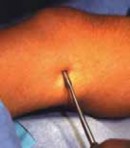

TECHNIQUES EPIPHYSIODESIS OF THE FEMORAL PHYSIS DISTALLY OR THE TIBIAL PHYSIS PROXIMALLYPreparation of the Physis 1. A metal marker is placed over the skin and under the image intensifier, and the level of the physis is identified at its peripheral area (either medially or laterally) (TECH FIG 1A).

2. A 3-mm skin incision is made with a scalpel at the level of the physeal plate on the peripheral side (medially or laterally) (

TECH FIG 1B

).

3. The scars of the percutaneous epiphysiodesis are small and have an acceptable appearance (

FIG 1

FIG 1 • Very small leg scar after a percutaneous epiphysiodesis of the femoral physis distally.